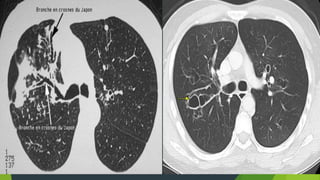

Dấu hiệu trực tiếp: Dày thành phế quản

 Khi phế quản bị dãn, vách dày

rầy xe lửa, hình ảnh này thấy

quang phế quản, hoặc phim CT

Dãn phế quản

 Dạng ống

 Dạng tràng

hạt

 Dạng kén

hoặc túi

X-Quang

-Biểu hiện các đám mờ hình ống do phế quản bị lấp đầy

chất nhầy

-Thành phế quản dày không đều , đường ray xe lửa, hình

súng hai nòng

- Có các ổ sáng nhỏ giống hình giả tổ ong, ổ sáng với

mức dịch

- 7- 30% giãn phế quản chụp phim phổi không thấy bất

thường

- CT là tiêu chuẩn vàng để chuẩn đoán giãn phế quản